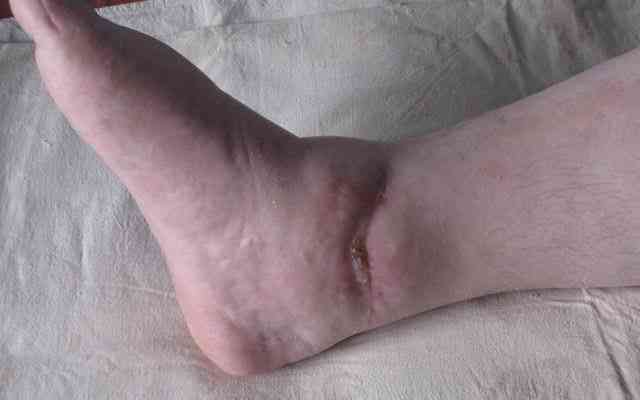

Если принять в качестве причины развития инфекции в области внутренней лодыжки трофические нарушения обусловленные неустраненным подвывихом стопы, то можно предположить что его устранение улучшит ситуацию. На представленной фотографии данных за гнойный артрит нет, имеется местное нагноение мягких тканей. Я бы попробовал накостный остеосинтез малой берцовой и мощный болт стяжку проведенный через отверстие в пластине на медиальную поверхность вне зоны инфекции, с обязательным дренированием и ревизией инфицированной области.

Коллеги, благодарю еще раз за дискуссию и советы. Объяснив пациентке о необходимости артродеза, она пока воздержалась от операции, мотивируя, что, собственно, боли ее и не очень-то беспокоят (ведь могу ходить!), хотя я сильно сомневаюсь о достаточно длинной компенсации. Кстати, свищ у внутренней лодыжки закрылся самостоятельно через 3-4 дня. Таким образом, на настоящее время проблема решена (остеосинтез - напрасная операция), а к артродезу она еще не готова психологически. Будем ждать, и, наверно, не так уж и долго осталось. О развитии событий, если уважаемый Ортофорум не возражает, проинформирую.